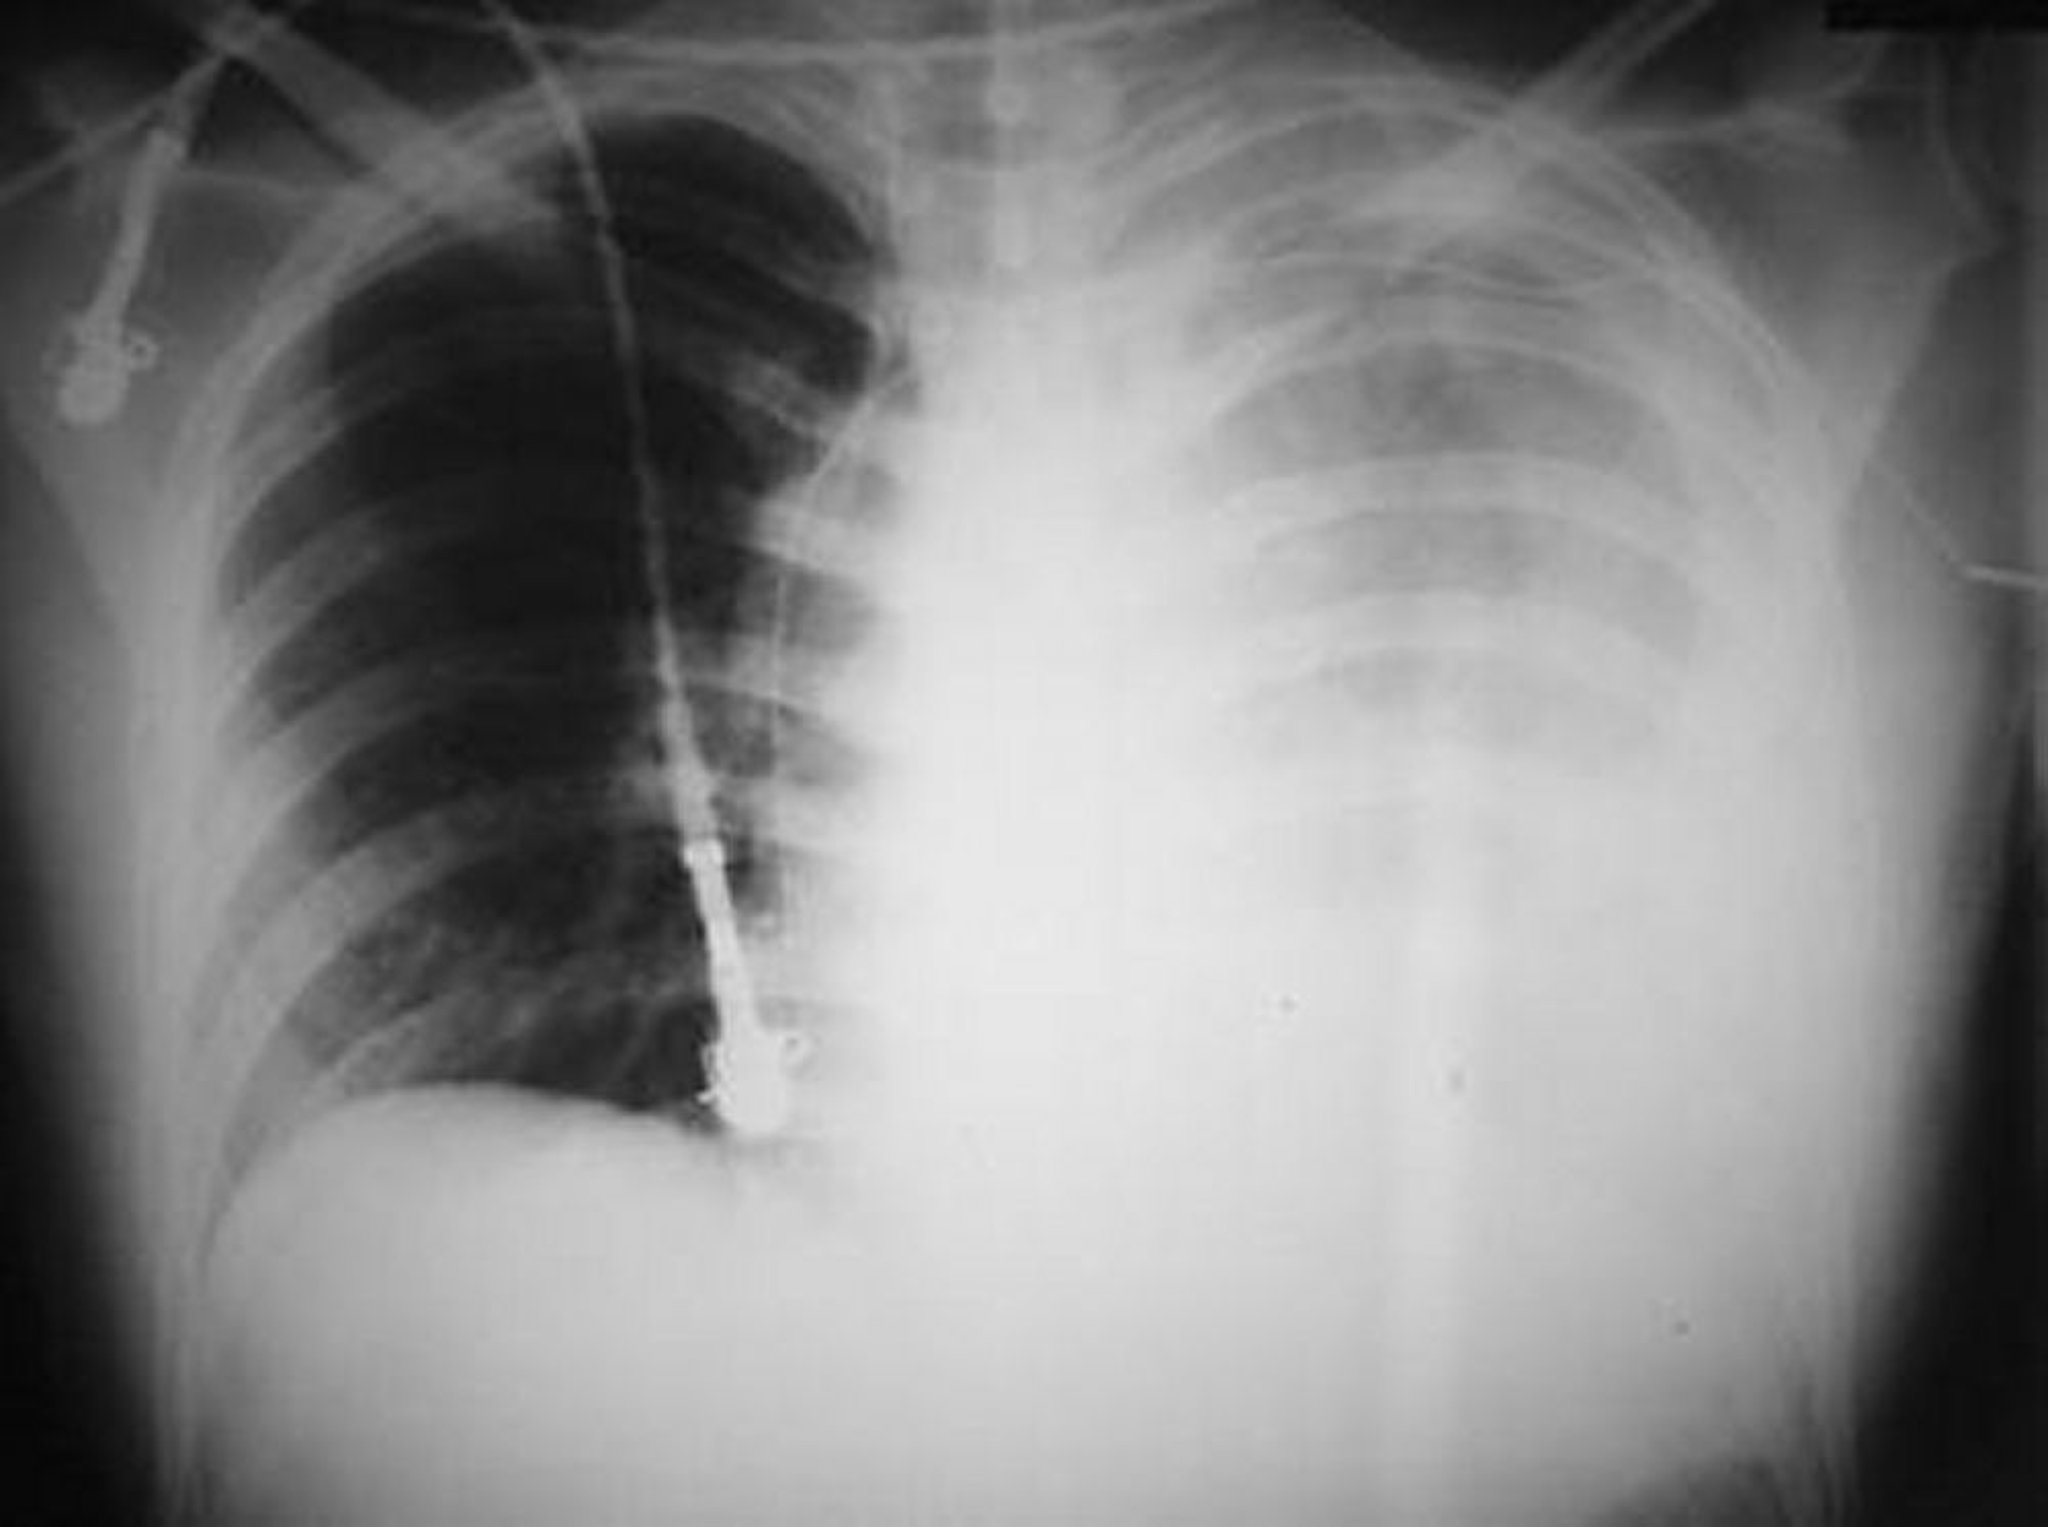

Dieses Foto zeigt einen massiven linken Hämothorax nach einer Schussverletzung in der linken Brust.